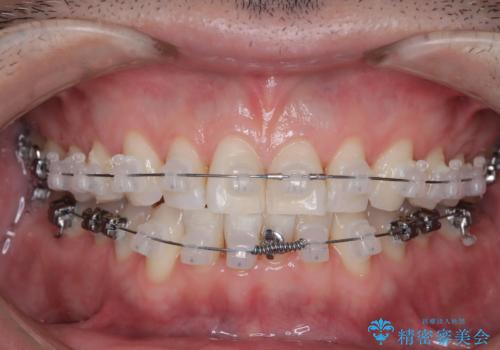

定期健診で歯並びを相談 セラミックブラケットでのワイヤー矯正例

- インシグニア デイモンクリア

- 治療計画

- 定期健診の際に、下顎前歯のガタつきが年々悪化しているとの相談を患者様より頂戴しました。下顎前歯の叢生(ガタつき)程度や患者様の希望もあり、非抜歯でも無理のない範囲と考えワイヤー矯正にて治療計画を立案しました。着色の少ないセラミックブラケットを使用しています。